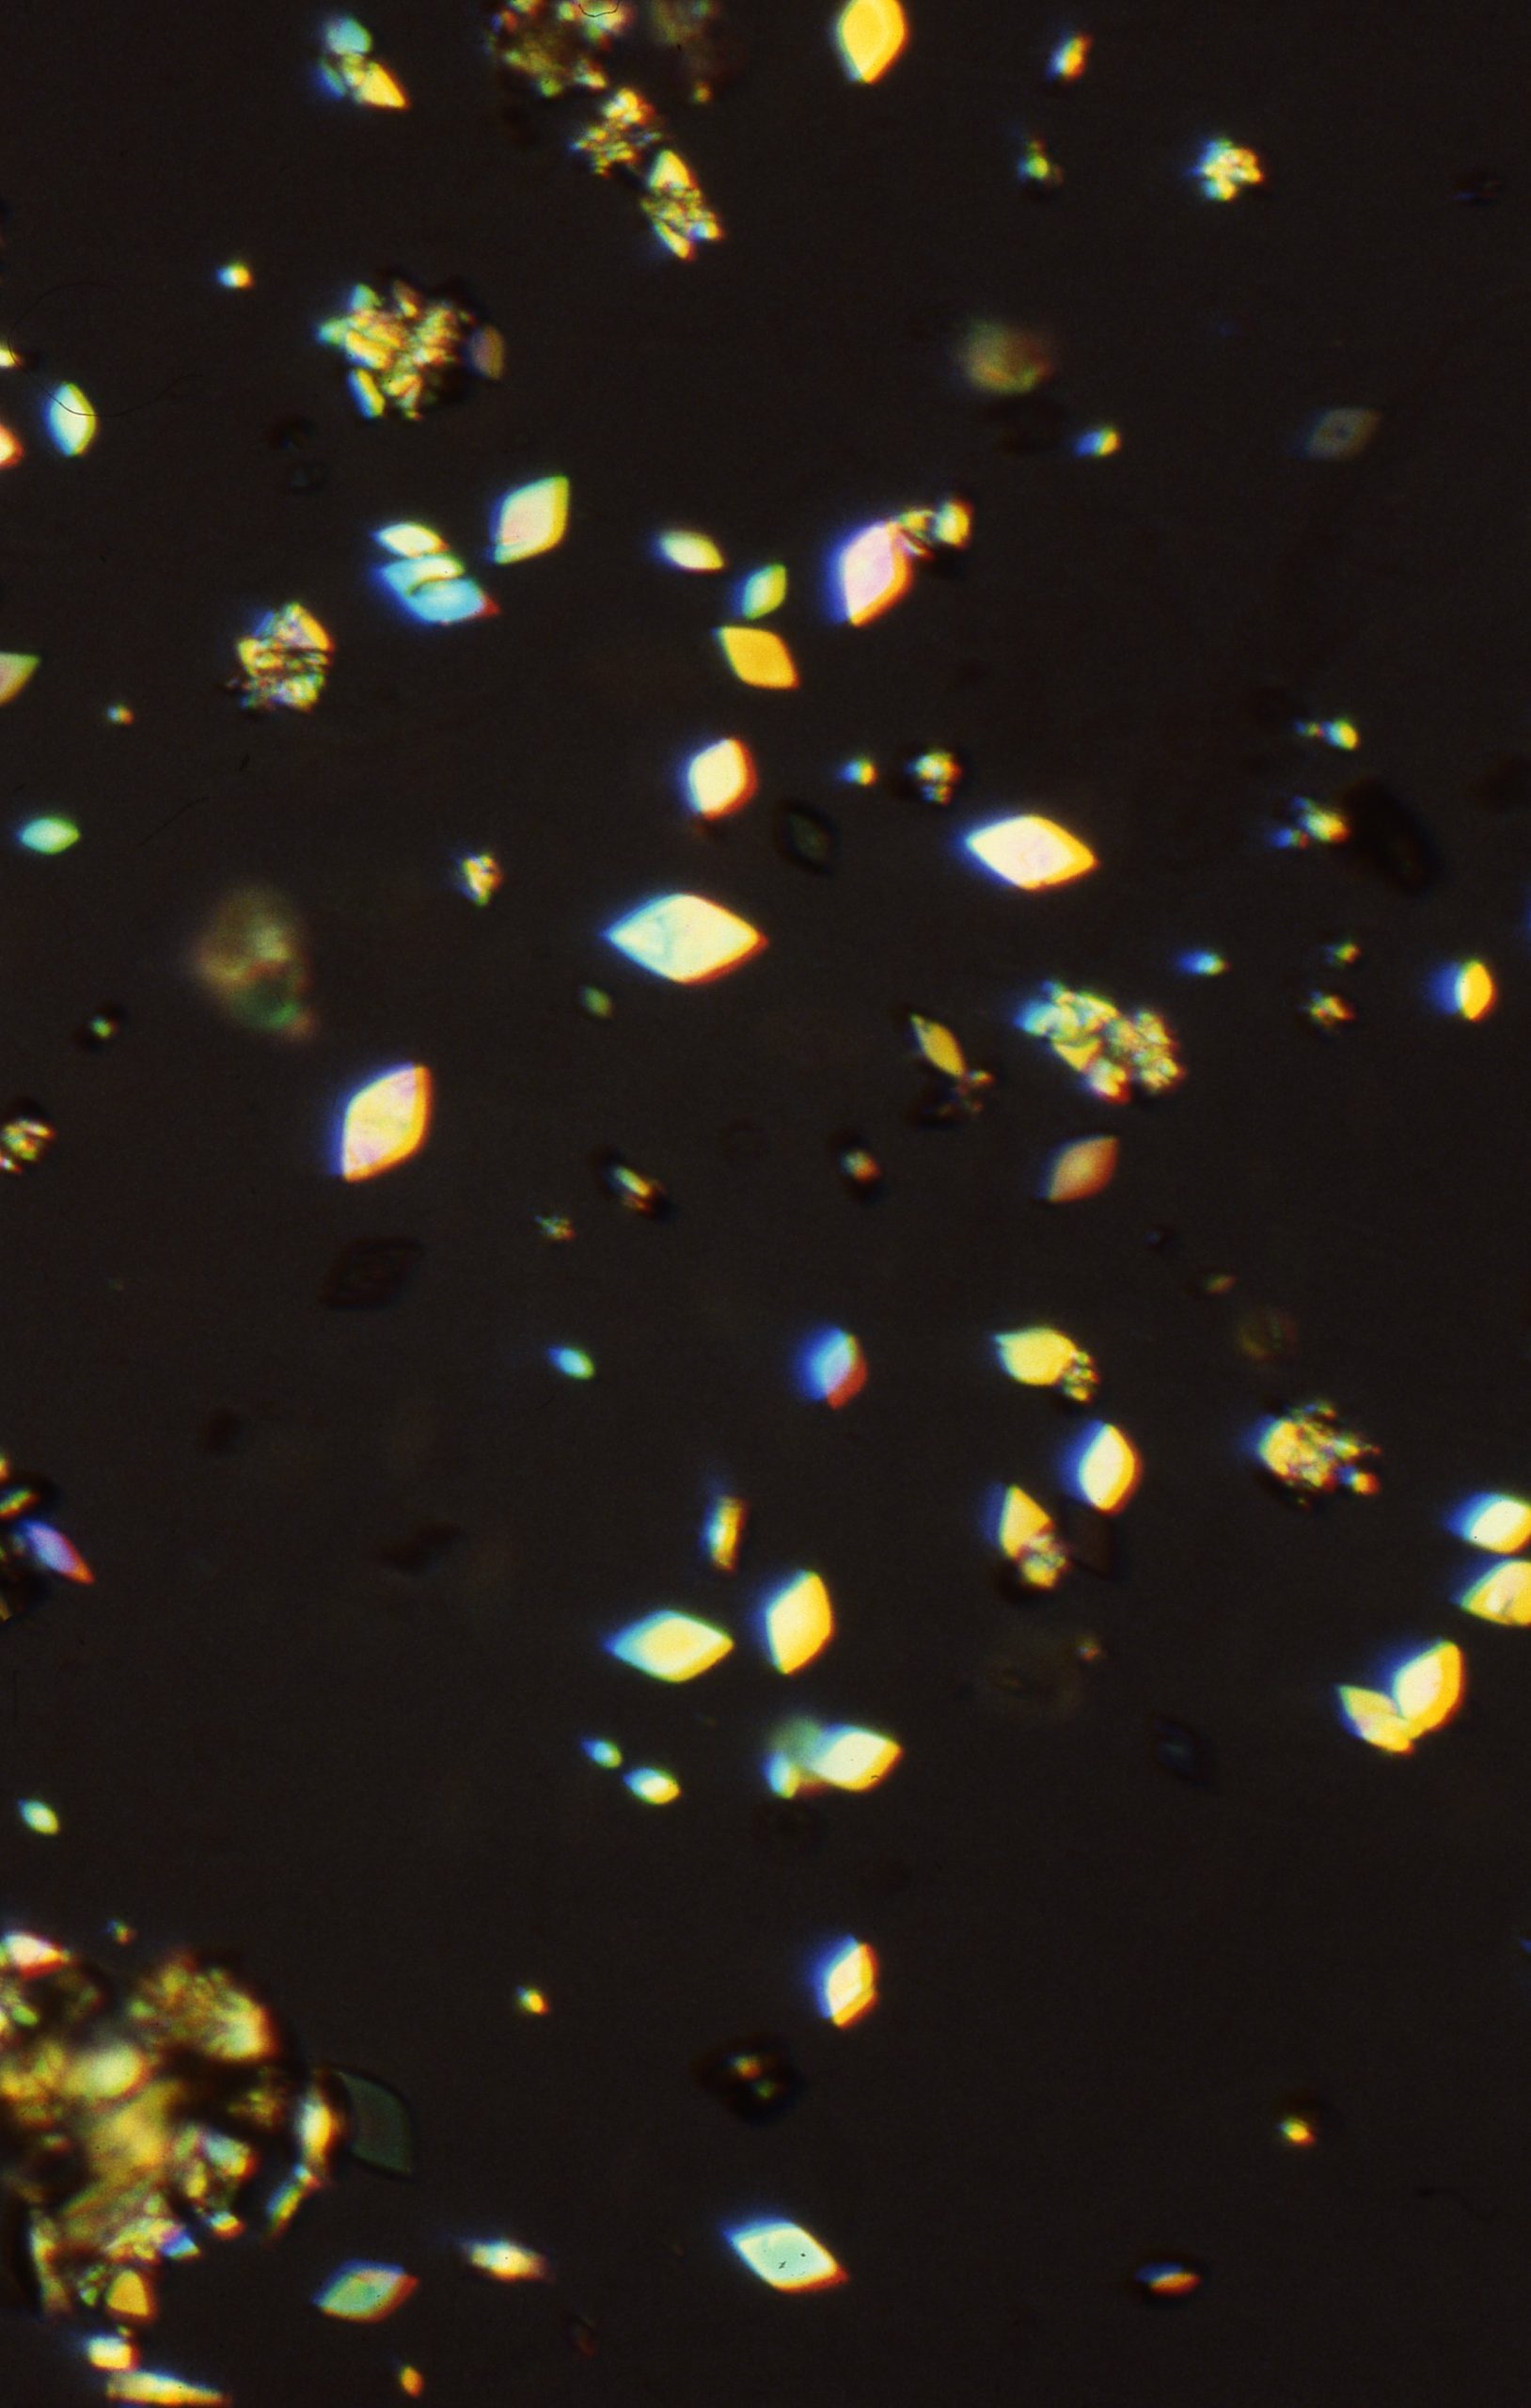

Uric acid crystals are found in acid urine, the crystal vary more in morphology than any other type of crystalThe morpholoy varies from needles, hexagonal, whestone forms, rosttes or rhombic plates Mag 10X Mag 10X Mag 10xX Mag 40X Mag 40X Mag 40X Mag 40x Mag 40X The above microphotographs are uric acid crystal with polarized light